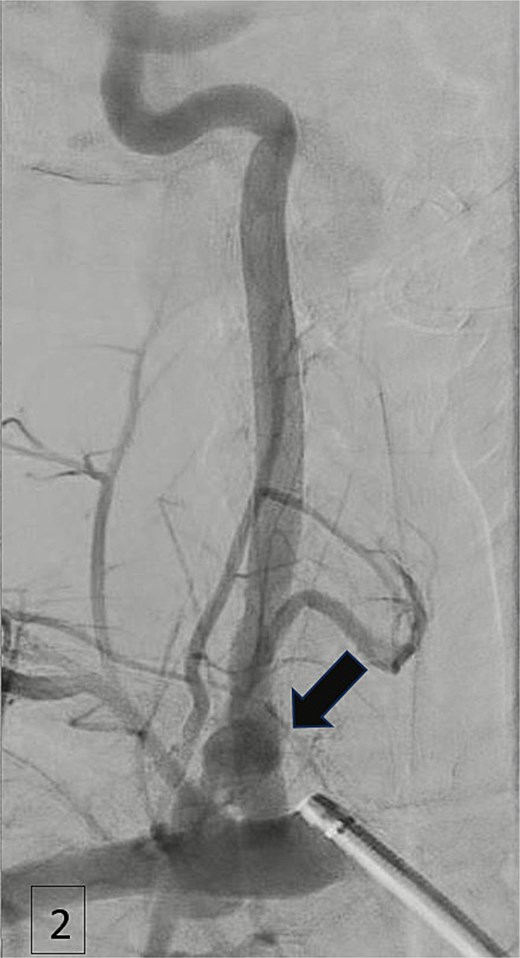

An urgent CTA revealed contrast extravasation from the proximal left vertebral artery, ~1 cm from its origin at the subclavian artery (Fig. 1). He was immediately taken to the angiography suite. Via left brachial access, a balloon-expandable covered stent (4 × 29 mm) was deployed, completely sealing the injury and restoring flow (Fig. 2). Post-procedure imaging confirmed no further extravasation (Fig. 3). The patient stabilized, vasopressors were weaned, and he was discharged without neurologic deficits. The patient’s clinical course and management are summarized in a timeline (Fig. 4).

Angiogram demonstrating arterial injury following catheter insertion (arrow).